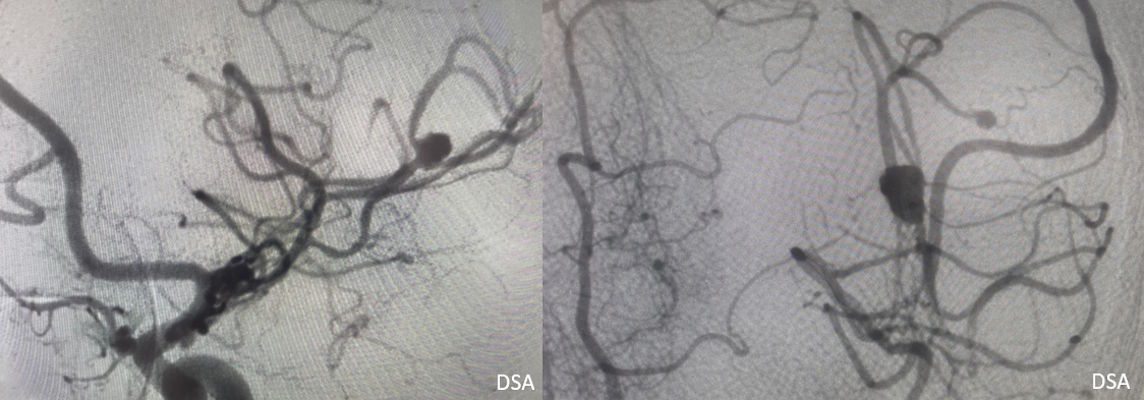

- DSA görüntülemede (G) sol MCA M2 segmentinde anevrizmatik dolum fazlalığı izleniyor (ok). Bu anevrizmaya eş zamanlı koil işlemi yapılıyor (oklar) ve işlem sonrası kontrol BT anjiografi görüntüsünde (H) metalik koil materyali izleniyor (ok).